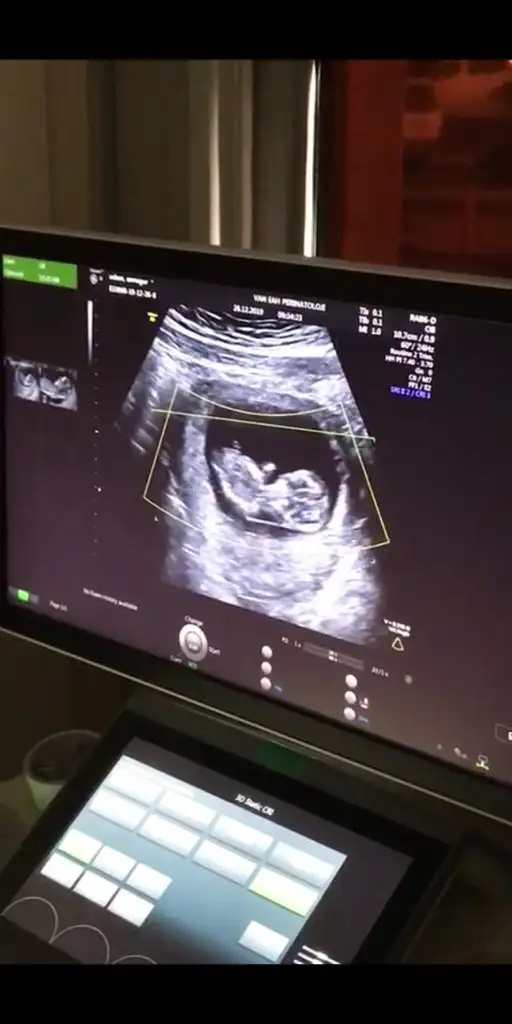

12 haftalık görüntü lütfen cinsiyet tahmini yapar mısınız

• Screenshot_20191227-194339.webp

Screenshot_20191227-194339.webp

20,3 KB · Görüntüleme: 40